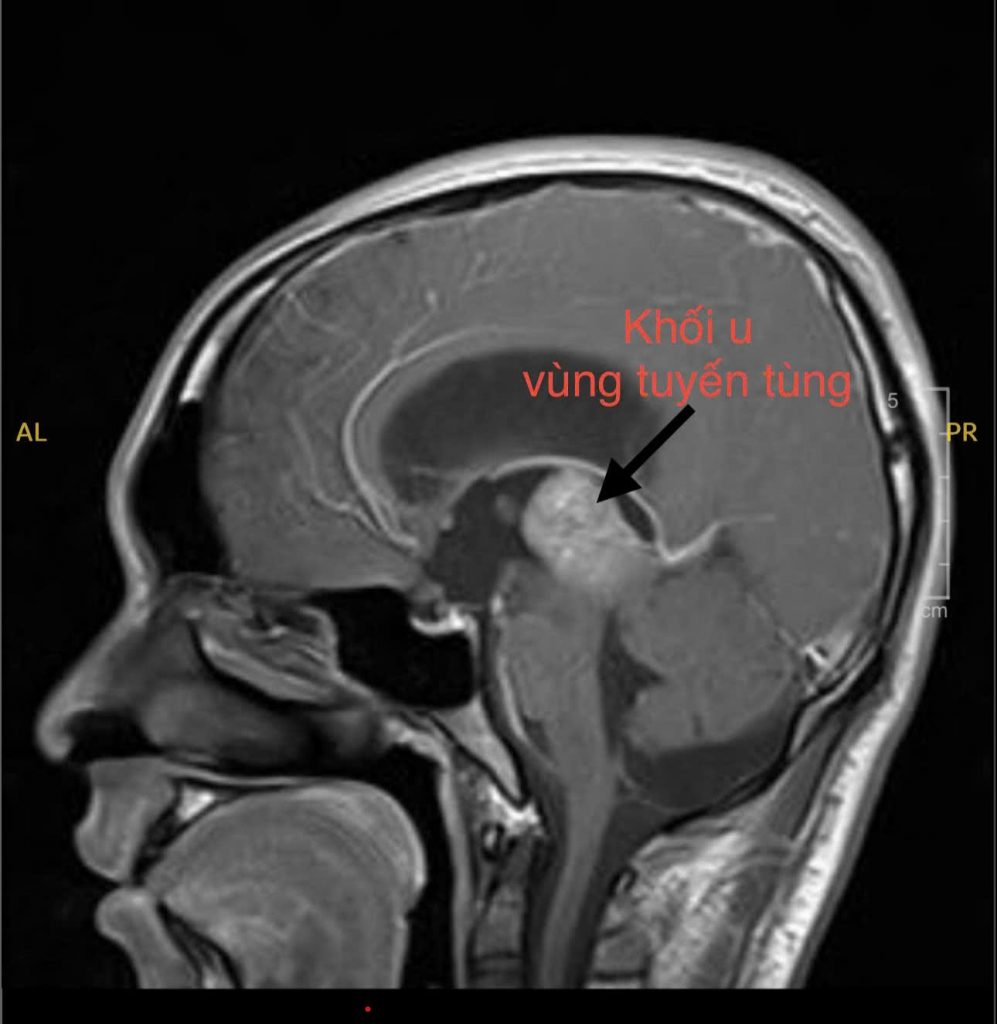

Tại đây, em được chỉ định chụp MRI não thì phát hiện có khối u vùng tuyến tùng – một dạng khối u nằm sâu giữa não, có thể gây chèn ép và cản trở đường lưu thông dịch não tủy. Đây chính là nguyên nhân khiến áp lực nội sọ tăng lên, gây ra những triệu chứng nặng nề mà em trải qua.

Hình ảnh MRI khối u vùng tuyến tùng